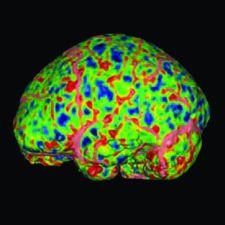

Vitrea software is Vital Images’ advanced visualization solution that creates 2D, 3D and 4D images of human anatomy from CT and MR image data. With this productivity-enhancing tool, physicians can easily navigate within these images to better understand disease conditions. The Vitrea software addresses specialists’ needs through various software options for cardiac, colon, vessel probe and other applications. In addition, Vitrea software utilizes an intuitive clinical workflow and automatic settings to improve speed and simplicity. Other capabilities and partnerships with PACS providers expanded physicians’ access to Vitrea software throughout an enterprise.